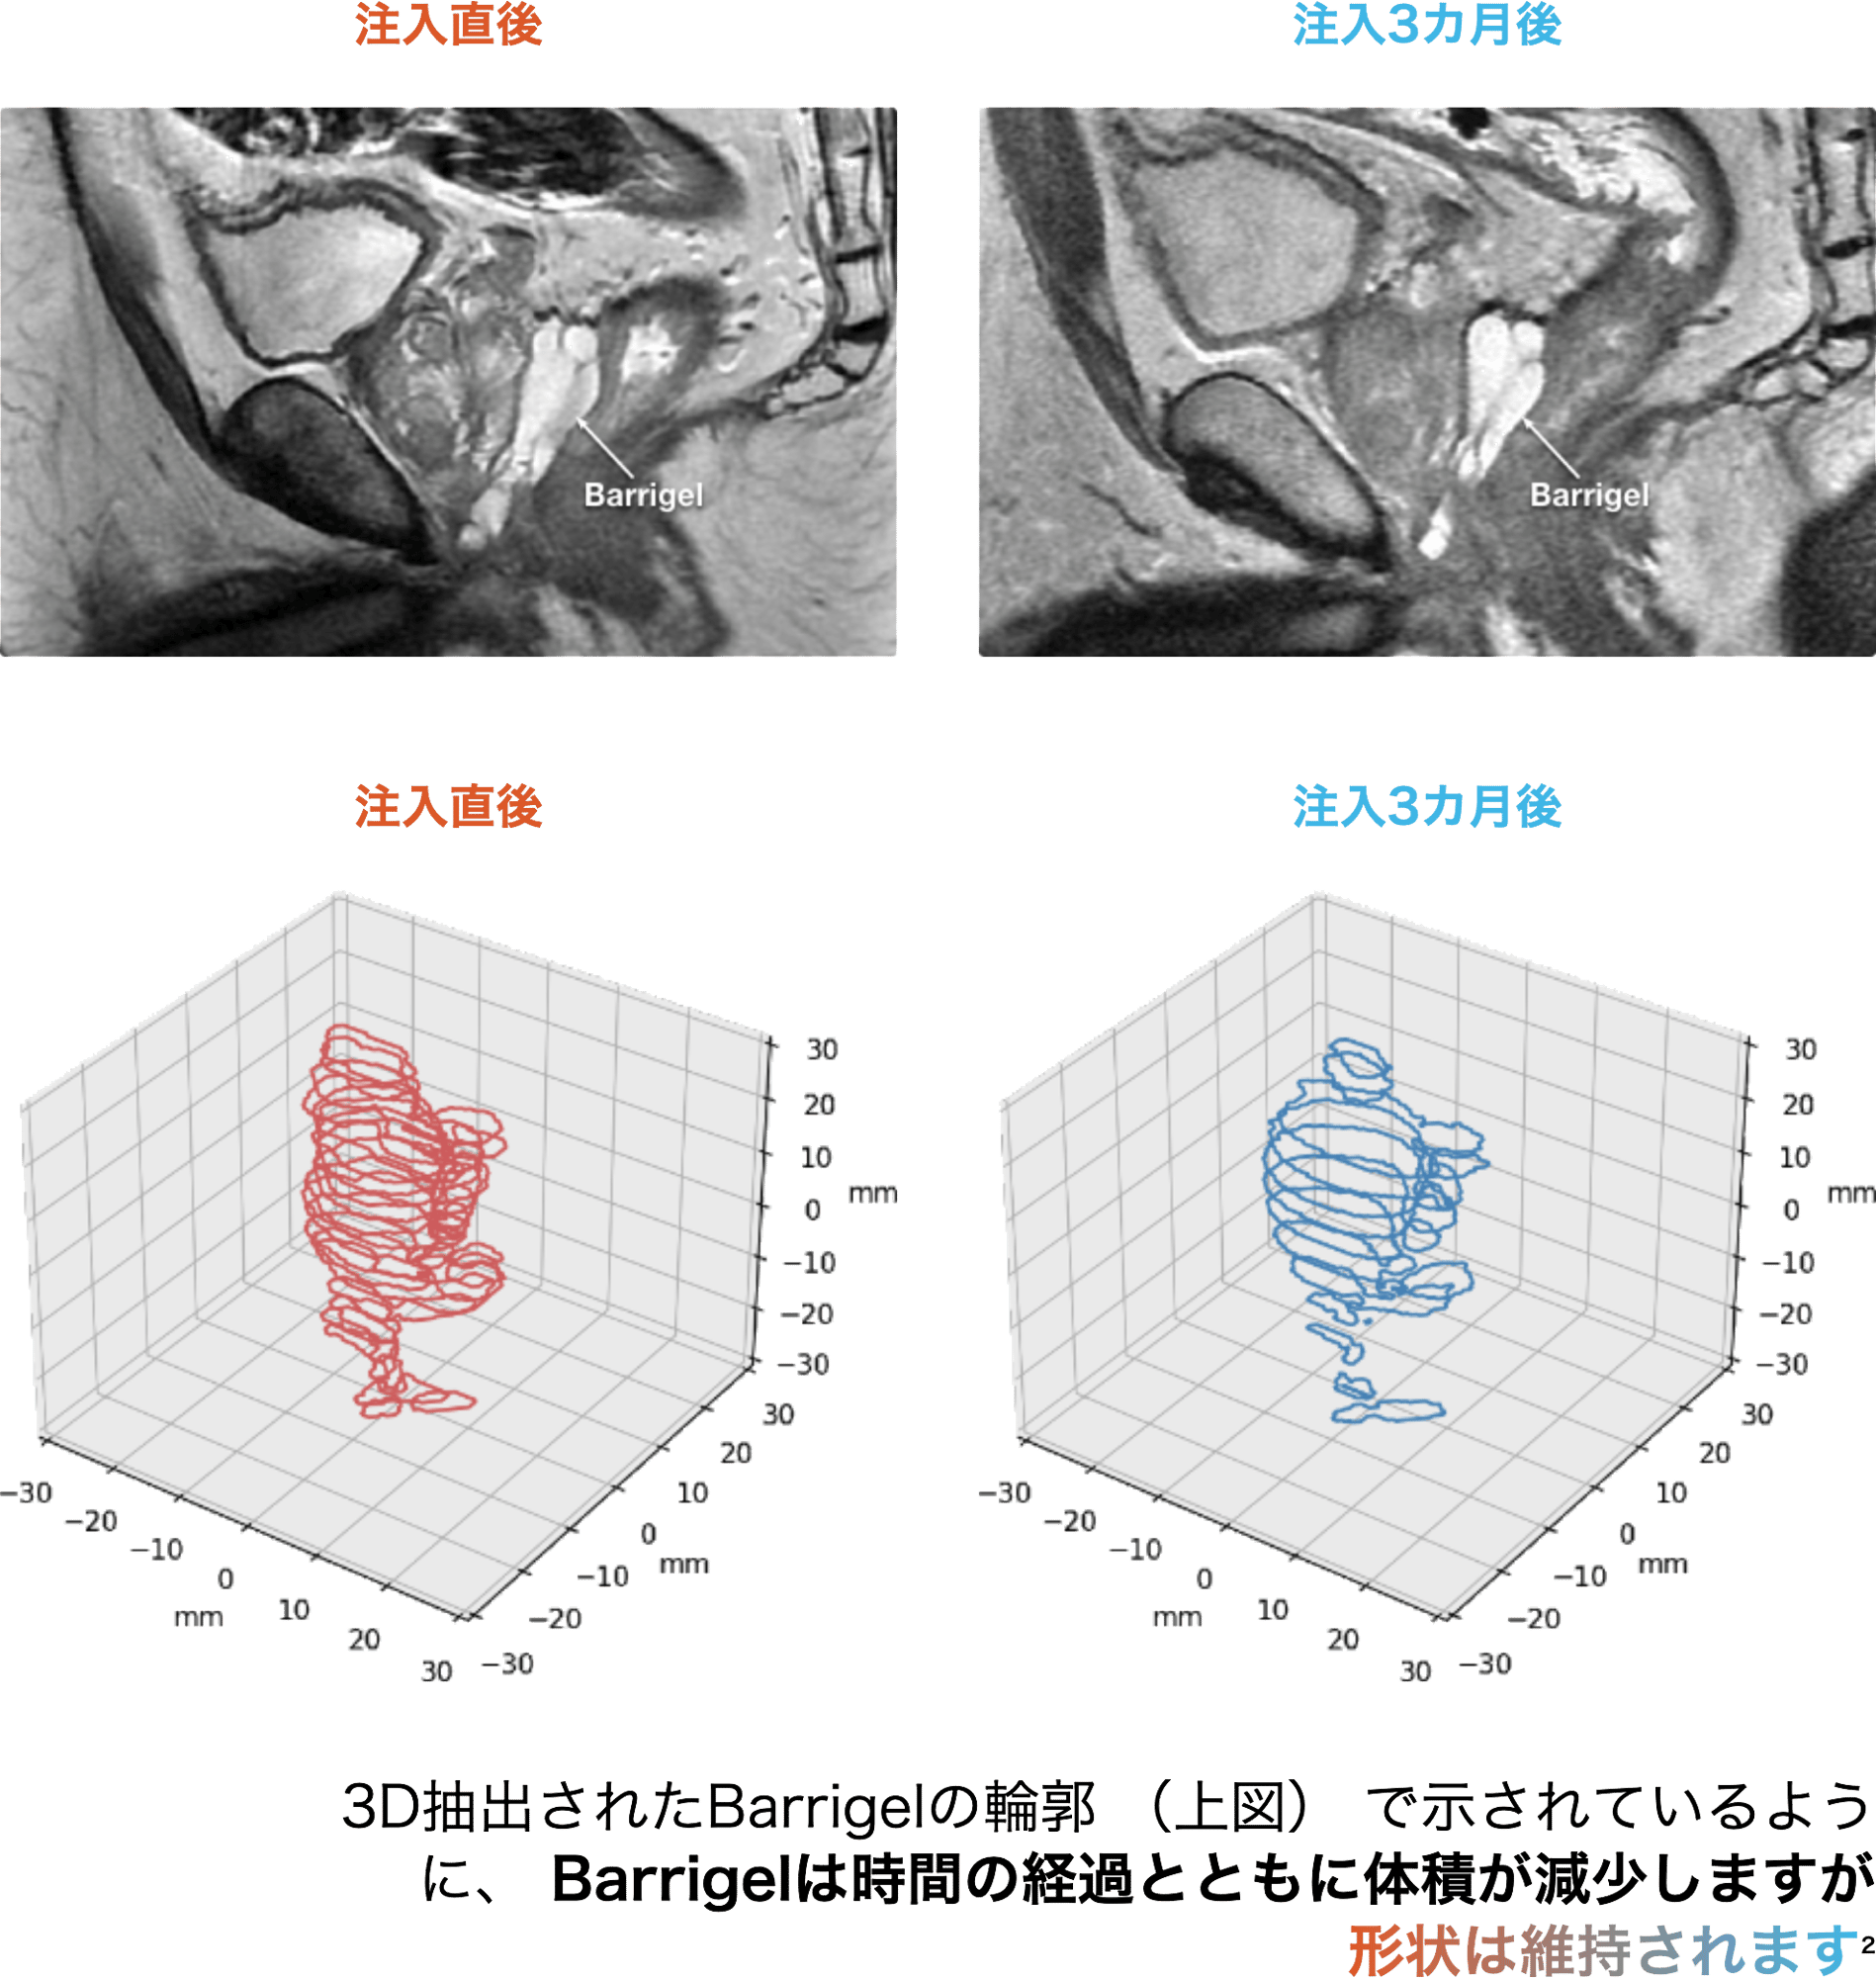

吸収時にも安定したスペースが認められた

患者の例